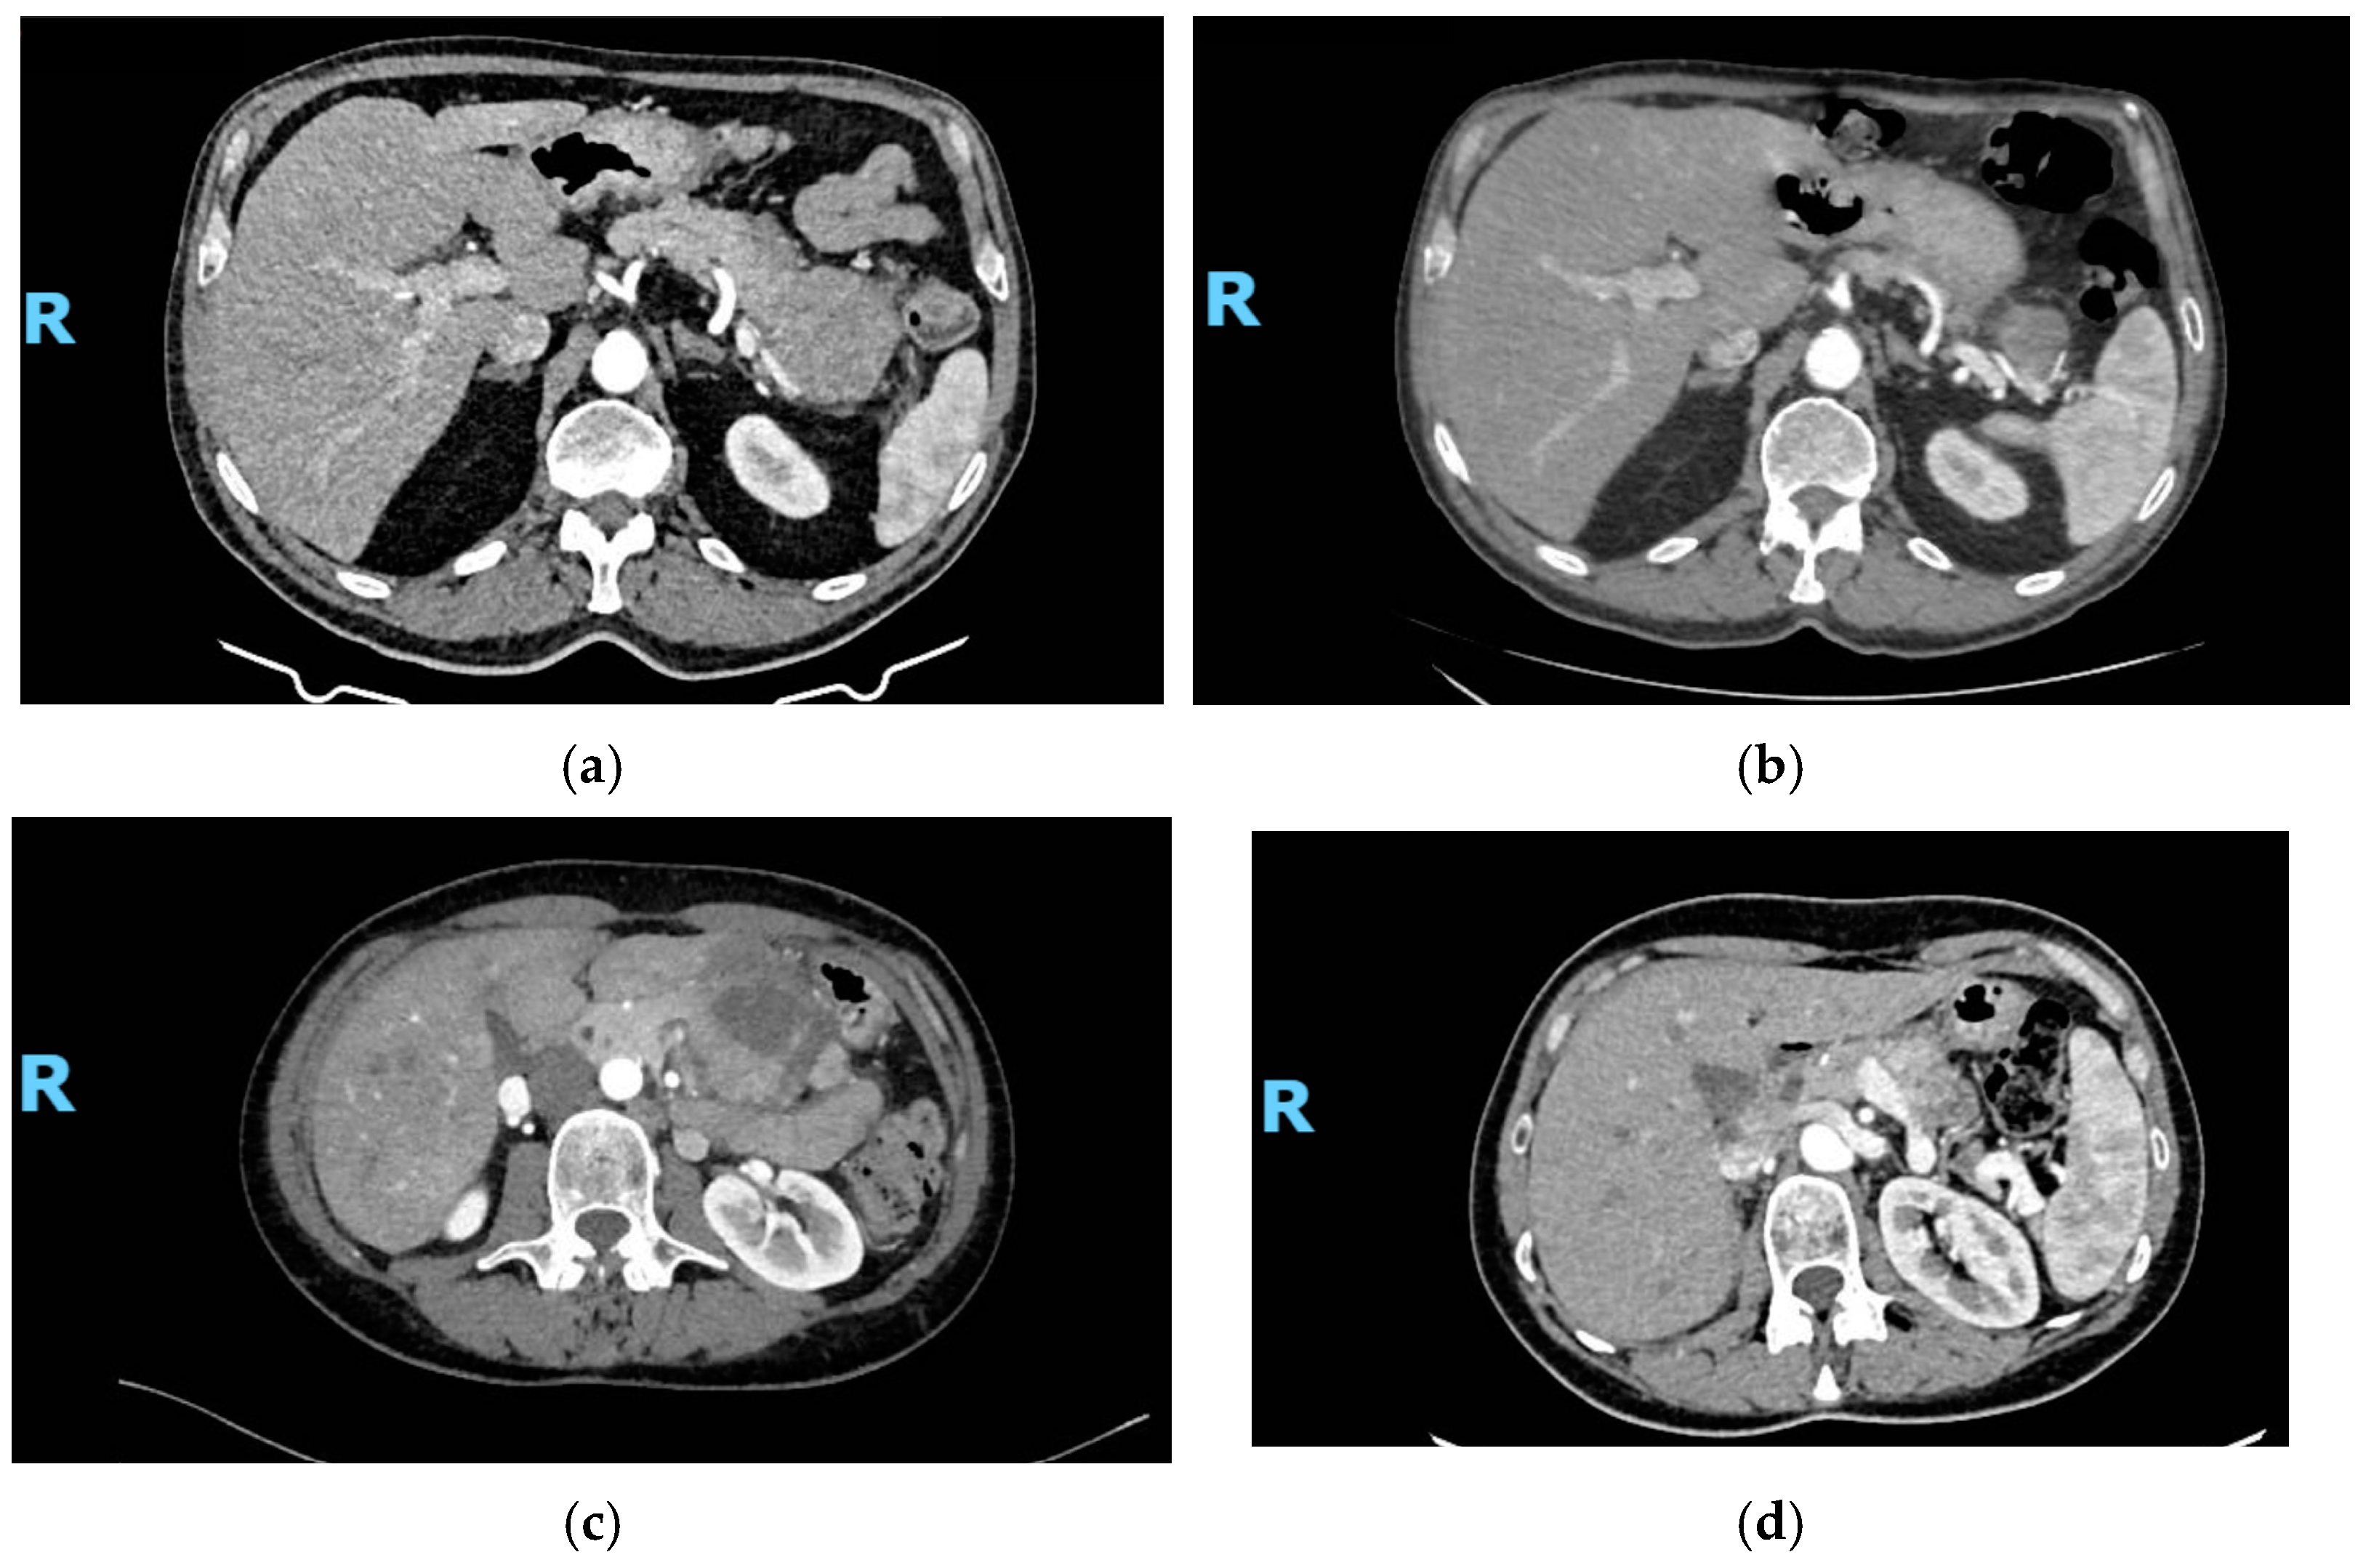

At the data cut-off analysis in October 2023, after a median follow-up of 45.9 months (mo.) each patient completed at least two cycles of oxaliplatin–fluoropyrimidine chemotherapy treatment. Eleven patients were treated with XELOX and seventeen with FOLFOX. For all patients, SSA treatment was prescribed within three months from day one of the first cycle of chemotherapy. The median time under oxaliplatin–fluoropyrimidine plus SSA combination therapy was 11.4 mo. Of the 32 patients enrolled, at data cut-off, 12 patients (37.5%) progressed or died, while 20 (62.5%) were still in follow-up. Up to 22 patients experienced tumor shrinkage (68.7%), with an overall response rate (ORR) according to RECIST v. 1.1 of 25% with 8 patients reporting a partial response (PR) as best response on treatment, while 20 patients (62.5%) had disease stability (SD). Figure 1 shows the waterfall plot of responses. The median duration of response (DoR) was 21.3 mo. Disease control rate (DCR) was 87.5%. Four patients (12.5%) were primary refractors to study treatment combination and had PD as best response at the first tumor evaluation. Despite no complete response being seen according to RECIST v. 1.1, in nine patients (28.1% of the overall population) tumor shrinkage was enough to allow a radical surgery on residual tumor lesions, including both primitive tumor and metastases, even in cases of high burden of disease at baseline. Figure 2 shows an example of significant tumor shrinkage in two pancreatic NET patients referred to radical surgery after treatment. The median PFS in the overall population was not reached (NR) due to paucity of events. The estimated mean PFS of the entire population at data cut off was 51.8 mo. (95%CI 38.3–65.3 mo.) (Supplementary Materials, Figure S1). Similarly, median overall survival (OS) has not yet been achieved (NR), due to the low number of events. The estimated mean OS was 62.2 mo. (95%CI 51.1–73.2 mo.) (Supplementary Materials, Figure S2).

Figure 2. Best response in two patients treated with FOLFOX + SSA: (ac) CT-scans at baseline; (bd) CT-scans after VI cycles. R: right.